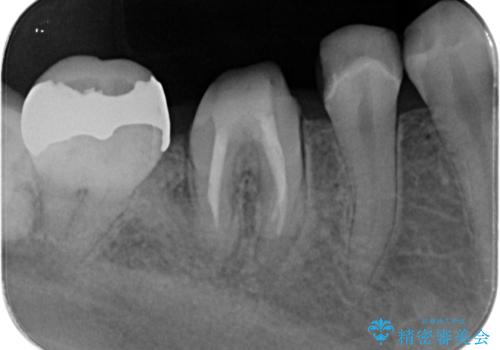

- メンテナンスで来院された患者様です。

歯茎が腫れたとの事で歯の神経が失活していたので精密根管治療を行い、ジルコニアクラウンで治療を行いました。

- ジルコニアクラウンスタンダード・仮歯 12.1万円 精密根管治療(イニシャルトリートメント)・ファイバーコア 13.2万円費用は治療当時の料金となります